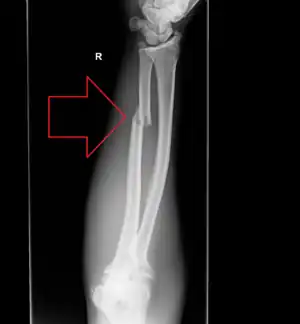

| Isolated fracture of the ulna (known as a nightstick fracture) | |

An ulna fracture is a break in the ulna bone, one of the two bones of the forearm.[3] If the fracture occurs as a single break in the middle of the ulna it is known as a nightstick fracture.[2] It; however, is often associated with a dislocation or fracture of the radius, the other forearm bone.[4][5] Complications may include nonunion.[1]

- Nightstick fracture is a fracture of the middle portion of the ulna without other fractures, and with both wrist and elbow joints preserved.[7]